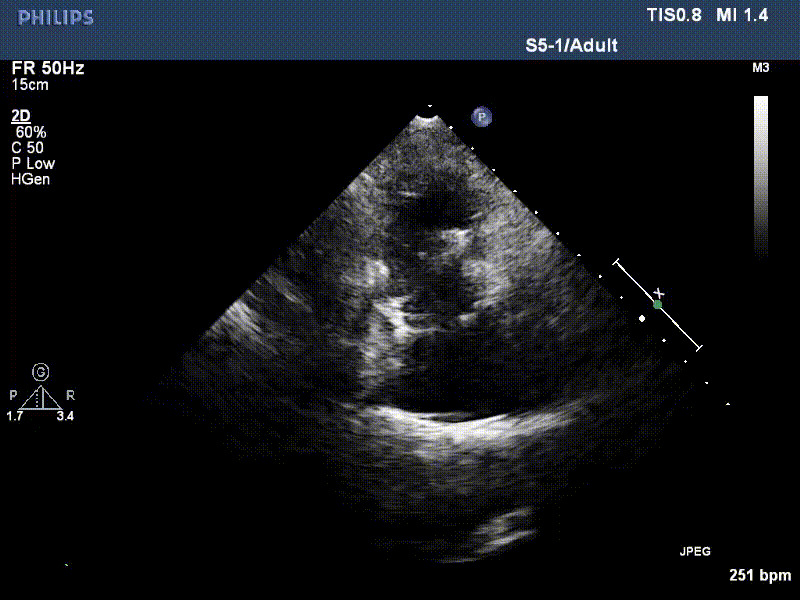

1年前,兩例患者因難治性雙下肢水腫輾轉(zhuǎn)多家醫(yī)院尋求救治,考慮到兩例患者高齡、基礎疾病多、STS評分高,不適合傳統(tǒng)外科開胸手術(shù),葛均波院士及其團隊周達新教授、潘文志教授、張源博士、陳莎莎博士、陳丹丹博士聯(lián)合心外科王春生、魏來主任,麻醉科繆長虹、郭克芳主任以及心超室的潘翠珍教授、李偉教授共同討論決定,采用我國創(chuàng)新器械LuX-Valve Plus經(jīng)血管三尖瓣置換系統(tǒng)為患者進行手術(shù)。相較于第一代產(chǎn)品LuX-Valve,LuX-Valve Plus經(jīng)血管三尖瓣置換系統(tǒng)對輸送系統(tǒng)進行了全面升級,實現(xiàn)了經(jīng)頸靜脈入路的方式,進一步減小了手術(shù)風險和對患者的創(chuàng)傷。目前隨訪1年心超結(jié)果顯示,三尖瓣極重度反流消失,人工三尖瓣瓣膜穩(wěn)定牢固,瓣葉活動度良好,右心室及下腔靜脈明顯縮小,心輸出量增加。兩位老人手術(shù)后沒有出現(xiàn)過胸悶氣促的癥狀,下肢水腫緩解,活動耐力提升,生活質(zhì)量也大為提高。

圖2 患者植入LuX-Valve Plus后,1年隨訪心超提示無三尖瓣反流